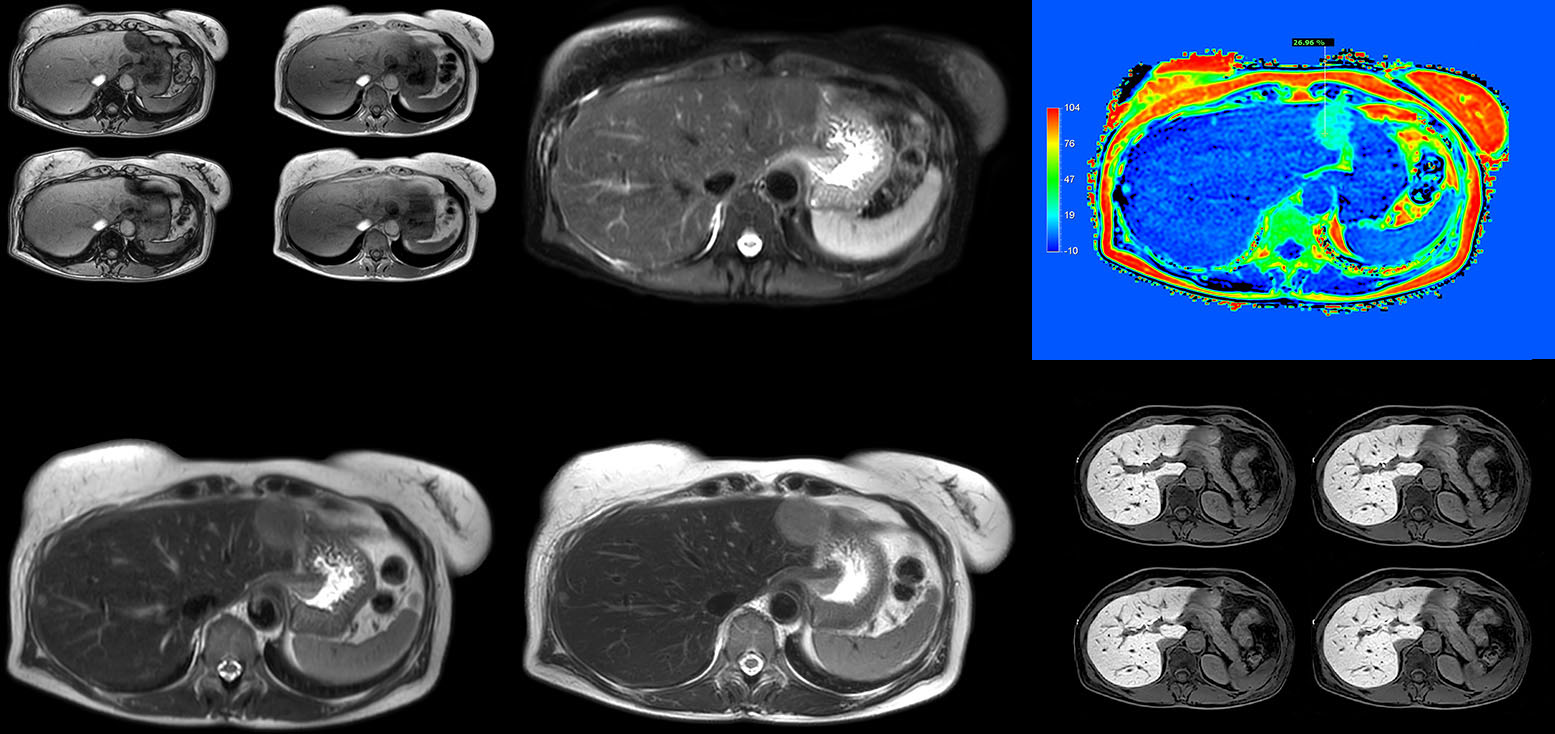

Robust motion correction and high spatial resolution with MultiVane XD

“Using MultiVane XD motion correction, we are now able to acquire high spatial resolution T2-weighted images without seeing relevant motion,” says Dr. Kukuk. “It’s a great technique to obtain high spatial resolution images of the pancreas or the liver, as well as the surrounding organs and tissues. MultiVane XD can be combined with dS SENSE parallel imaging, allowing us to reduce specific absorption rates (SAR), acquire high spatial resolution in short acquisition times, and at the same time reduce artifacts caused by motion in adjacent tissues and organs.”

“In comparison to single shot T2-weighted TSE, this approach with MultiVane XD motion suppression provides higher spatial resolution. In addition, it is especially valuable in patients who cannot hold their breath or have some disabilities. My impression is that this sequence has the potential to substitute for, or even replace, the T2-weighted single shot sequence in our liver exams, because of good and consistent delineation of small lesions.”

mDIXON Quant is a simple sequence to include in routine liver MRI

“We have performed a study comparing mDIXON Quant fat percentages with results from histopathology. The correlation with different histologic methods was very good and also the correlation with MR spectroscopy was far above 0.9 – a nearly perfect correlation,” says Dr. Kukuk.

“So, this fast mDIXON Quant sequence allows us to diagnose, quantify, and follow up – that’s the real advantage. Our gastroenterologists were easily convinced, as they are well aware of the limitations of ultrasound and the risks of liver biopsy.”

“I would recommend acquiring mDIXON Quant routinely in liver MRI exams. It is fast, easy to use, and has been well evaluated [2,3]. The time investment is low and the benefit is high.”

Non-invasive liver fat quantification in a breathhold with mDIXON Quant

“Fatty liver disease is a common condition. Studies found a prevalence of non-alcoholic fatty liver disease in up to 44% in the general European population [1]. Liver fat cannot be quantified by ultrasound or CT, so biopsy has been the way to quantify fatty liver disease so far,” says Dr. Kukuk. “mDIXON Quant now allows non-invasive quantification of liver fat, which is valuable for both diagnosis and follow-up during dietary changes or therapy, for instance in hepatitis C.”

“The mDIXON Quant fat fraction maps provide quantitative information and also anatomical detail. The sequence is fast, usually taking about 16 seconds, which is just a breath hold for most patients. It definitely improves our efficiency.”